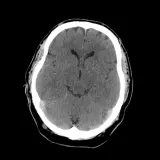

Over 2,100 interactive radiology cases, curated by radiologists for your level of training. Scroll, window, and view cases full screen — just like on PACS. Click linked findings in each writeup to jump straight to them on the image. Cases include sample reports, a focused discussion section, original illustrations, and videos.

Neuro Fellowship — a course tailored for fellows and practicing radiologists with in-depth reviews of advanced neuro topics like brain tumors, featuring rare diagnoses, differentials, and clinical pearls.

Casos totalmente interactivos con las herramientas que esperaría de un PACS: scroll, ventana, zoom, pan, mediciones, ROI y modo de pantalla completa.

• Anotaciones enlazadas

Anotaciones extensas resaltan los hallazgos clave directamente sobre los casos. Haga clic en los hallazgos enlazados dentro de la descripción del caso para saltar a su ubicación exacta en el estudio.

Aprenda con eficiencia gracias a hallazgos de imagen anotados e ilustraciones